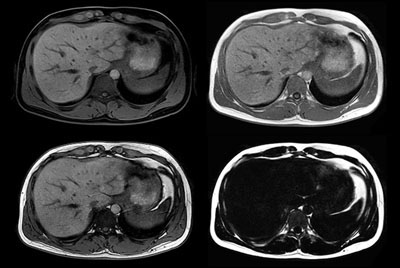

Liver quantification

Fatty liver with MR Elastography

Liver metastasis

Liver metastasis – Free breathing

Liver cyst

Liver with MRCP

Liver hemangioma with Compressed SENSE

Comprehensive Liver exam of focal liver lesions

Liver MR imaging

Comprehensive Liver imaging at 3.0T

Comprehensive Liver imaging at 1.5T

mDIXON Quant - Steatosis

Advanced Liver imaging

Liver imaging with MultiVane XD

Advanced Liver MR - mDIXON Quant